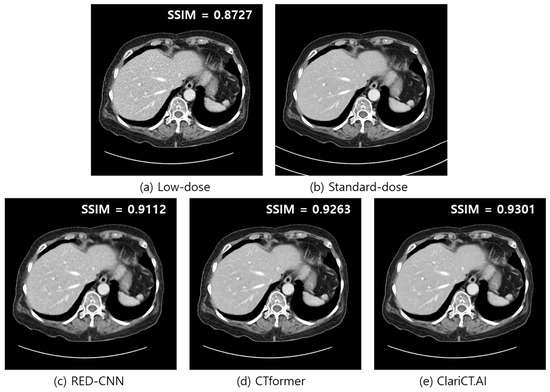

3.5. Auditing of DL Denoisers

| RSI ↓↓ | FR-IQA | NR-IQA | |

|---|---|---|---|

| SSIM ↑↑ | NIQE ↓↓ | ||

| RED-CNN | 0.28 ± 0.06 | 0.8725 ± 0.0279 | 9.58 ± 0.32 |

| CTformer | 0.21 ± 0.06 | 0.8917 ± 0.0254 | 9.93 ± 0.30 |

| ClariCT.AI | 0.15 ± 0.03 | 0.9005 ± 0.0248 | 9.06 ± 0.27 |